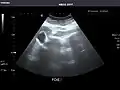

Right kidney

Renal ultrasonography

Ultrasonography of the kidneys is essential in the diagnosis and management of kidney-related diseases. The kidneys are easily examined, and most pathological changes in the kidneys are distinguishable with ultrasound.[7]

Kidneys: Right and left kidneys measure 11.5 cm and 12 cm in length respectively. No hydronephrosis. Small left lower pole kidney cyst.